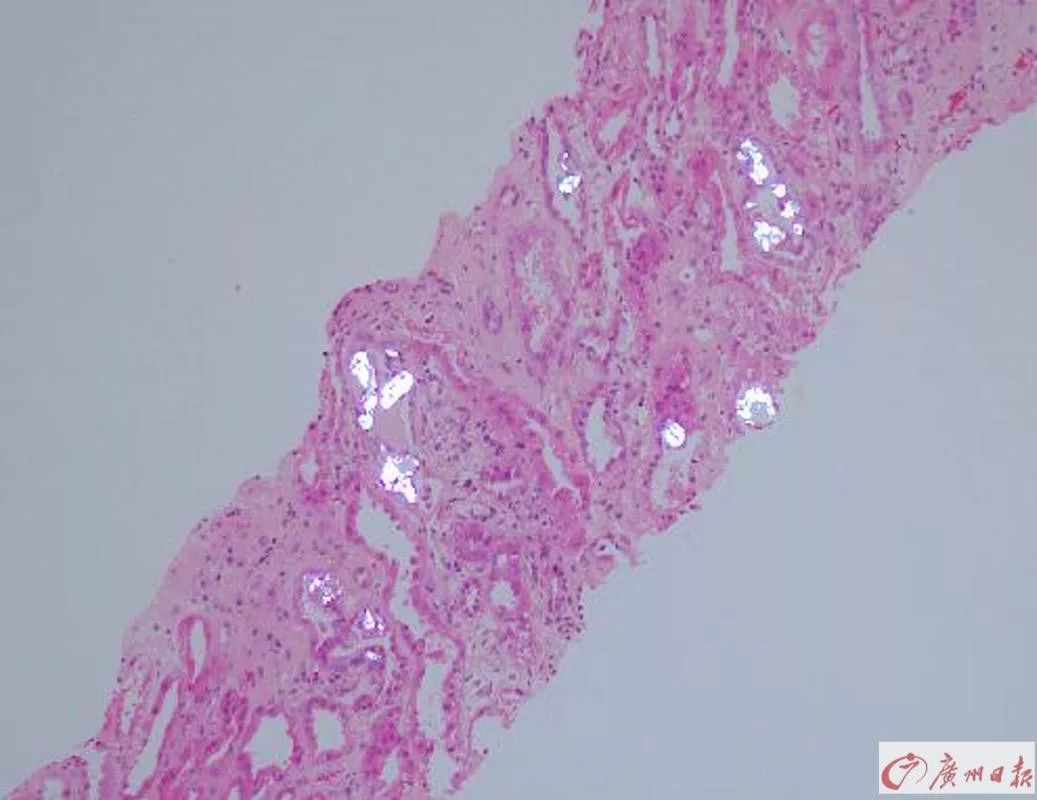

肾小管造影显示存在大量结晶沉淀物。(银白色部分)

两位患者的肾穿刺病理活检结果都提示——符合急性肾小管损伤。在住院将近半个月后,两人才陆续出院。“没想到喝了这个杨桃酒后果这么严重,以前都不知道杨桃有肾毒性啊。以后再也不敢喝了。”出院前,张先生说。